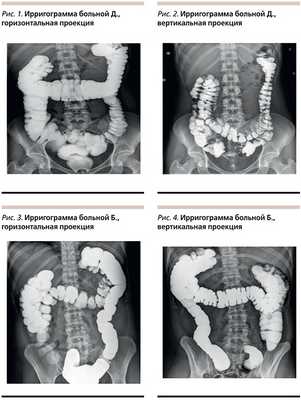

Наиболее информативным методом диагностики аномалий развития и положения толстой кишки является рентгенологический. Исследование позволяет сразу же определить положение толстой кишки в брюшной полости, форму и размеры всех ее отделов, подвижность при проведении исследования в положении больного стоя и лежа. Следующие клинические примеры продемонстрируют диагностическую ценность данного метода диагностики.

Пациентка Д. 26 лет обратилась с жалобами на боли в нижних отделах живота без связи с актом дефекации, нарушениями стула; вздутие живота, «живот как каменный». При ирригоскопии (рис. 1) толстая кишка удлинена, образует дополнительные петли в области селезеночного и печеночного углов, поперечно-ободочный отдел опускается до уровня L4-L5. Восходящий отдел также удлинен, купол слепой кишки в малом тазу на уровне ректо-сигмоидного перехода. В вертикальной проекции (рис. 2) печеночный угол смещается до уровня крыла подвздошной кости, купол слепой кишки и часть поперечно-ободочной кишки в проекции малого таза.

Пациентка Б. 37 лет на момент осмотра жалоб активно не предъявляет, периодически отмечает дискомфорт в мезогастрии, вздутие живота. Ранее была госпитализирована в связи с внезапно развившимся болевым приступом: вздутием живота, болями в правой подвздошной области. При обследовании данных за острую хирургическую патологию не выявлено, рекомендован прием спазмолитиков, эффект не стойкий. Через месяц вновь появились боли в мезогастрии, тошнота, вздутие живота. Нарушений стула не отмечает. При ирригоскопии (рис. 3) ободочная кишка удлинена, за счет поперечно-ободочного и восходящего отделов образует дополнительные петли в области селезеночного и печеночного углов, купол слепой кишки на уровне входа в малый таз, дополнительная петля печеночного угла опускается до уровня S1-S2. В вертикальной проекции (рис. 4) отмечается смещение правого фланка книзу, купол слепой кишки располагается на уровне ампулы прямой кишки.